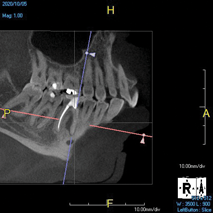

(1. ) Two-dimensional periapical radiograph of tooth No. 19 compared with a CBCT scan slice (0.1 mm) of the same tooth, which reveals a well-defined lesion that a patient can more easily understand.

Figure 1

(2.) Two-dimensional periapical radiograph of tooth No. 19 compared with a CBCT scan slice (0.1 mm) of the same tooth, which reveals a well-defined lesion that a patient can more easily understand.

Figure 2

The idea that a dentist may be incorrect in his or her diagnosis is distasteful, but a reality that this profession wrestles with on a daily basis. An image comparison can help to clarify this thought. The first image is a 2D radiograph of tooth No. 19 that includes the buccal cortical plate the lingual cortical plate and approximately 10 mm of trabecular bone compressed into a single image (Figure 1). Because the full width and volume of the tooth is included in the image, any existing pathoses could be masked or hidden in a fog of digital information. A CBCT scan of the same tooth provides more detail because it can present a slice (0.1 mm) of information from the center of the area in question (Figure 2). All of the extraneous information is eliminated, and the clinician and the patient have a more precise picture to evaluate. Furthermore, a periapical radiograph can be distorted by the angle of the cone to the sensor, whereas a CBCT scan has no distortion and is accurate in all views. With a CBCT scan, the clinician is able to state with certainty that a condition exists, and the patient is able to more clearly understand what his or her condition is when considering the available choices for treatment.